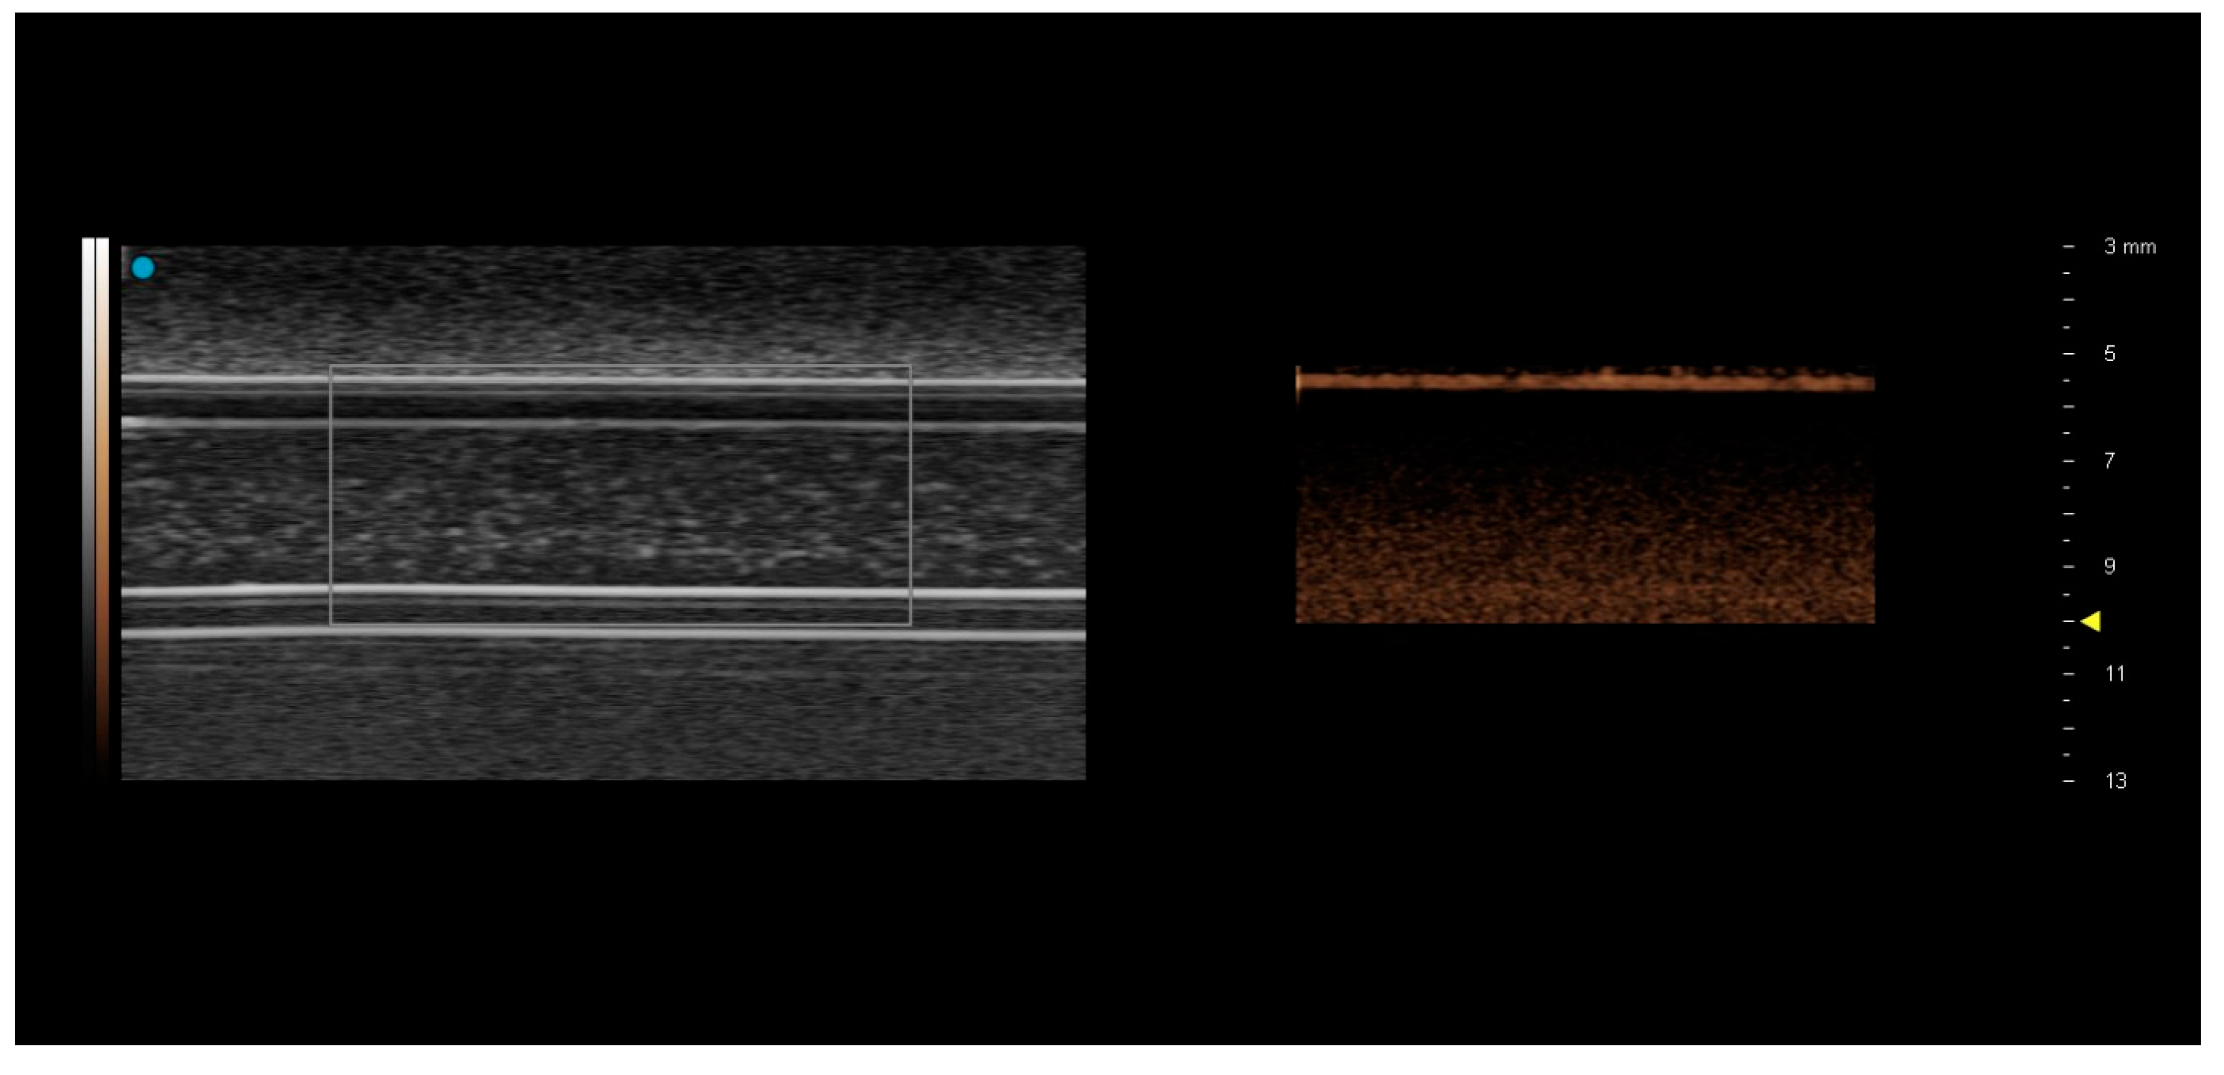

The Fujifilm Visualsonics Vevo 3100 MX250 probe was only able to visualise the contrast-filled superficial tubes in B-mode (Figure 4).

The matching CSIM image showed a bright line coincident with the upper level of the tubing, with a dark region immediately below the tubing suggestive of shadowing, either by the tubing or by contrast within the upper levels of the tubing. This was consistent for both contrast agents and both flow rates. Consequently, no analysis could be performed on these images.

Figure 4. Images acquired using the Vevo 3100 MX250 preclinical ultrasound probe from 3.2 mm diameter tubing at 1.0 cm depth. Tubing is filled with SonoVue. Only the superficial layer of the tube can be visualized in the contrast-specific imaging mode image on the RHS.